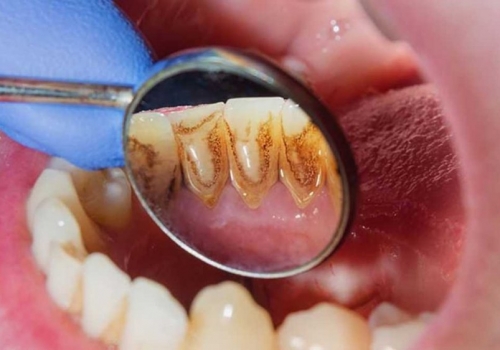

Parodontit, bütünlükdə parodont olaraq bilinən diş köklərini əhatə edən, dəstəkləyən və diş yuvasına fiksə edən xüsusi toxumaların, bağ aparatının və sümüyün iltihabıdır. Parodontit diş əti iltihabının gingivitdən sonrakı ikinci mərhələsi olub, gingivitdən fərqli olaraq müalicə edilmədiyində geri dönməyən degenerativ dəyişikliklərə, diş və onu əhatə edən sümük toxumasının itirilməsinə gətirib çıxara bilir. Parodontitin yaranma səbəbi bakterial plakdır. Lakin xəstəliyin inkişafında bir sıra yerli və ümumi faktorlar da rol oynaya bilir.

Parodontit tədricən dişətrafı sümük toxumasının itirilməsinə və bakterial plakın daha dərin təbəqələrə keçməsi ilə birlikdə ciddi dərinliklərə çatan sümük defektlərinin (və ya ciblərinin) yaranmasına gətirib çıxarır. Sümük toxumasının itkisi müəyyən bir zaman sonra dişlərdə ciddi hərəkətliliyin yaranmasına və qısa bir müddət sonra itirilməsinə gətirib çıxara bilir.

Parodontitin əsas əlamətləri bunlardır:

- Diş ətində şişkinlik və qızartı

- Diş ətlərində çəkilmə

- Ağız qoxusu